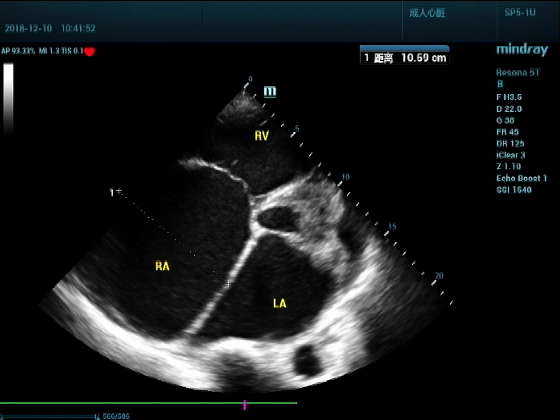

男,81岁,全身浮肿来住院

超声可见:左房,右房,右室明显增大,主肺动脉及右肺动脉增宽,二尖瓣中度反流,三尖瓣重度反流,肺动脉轻度高压,心律不齐

心包积液盆腔积液。淤血性肝增大,肝静脉增宽。(右心衰声像改变)